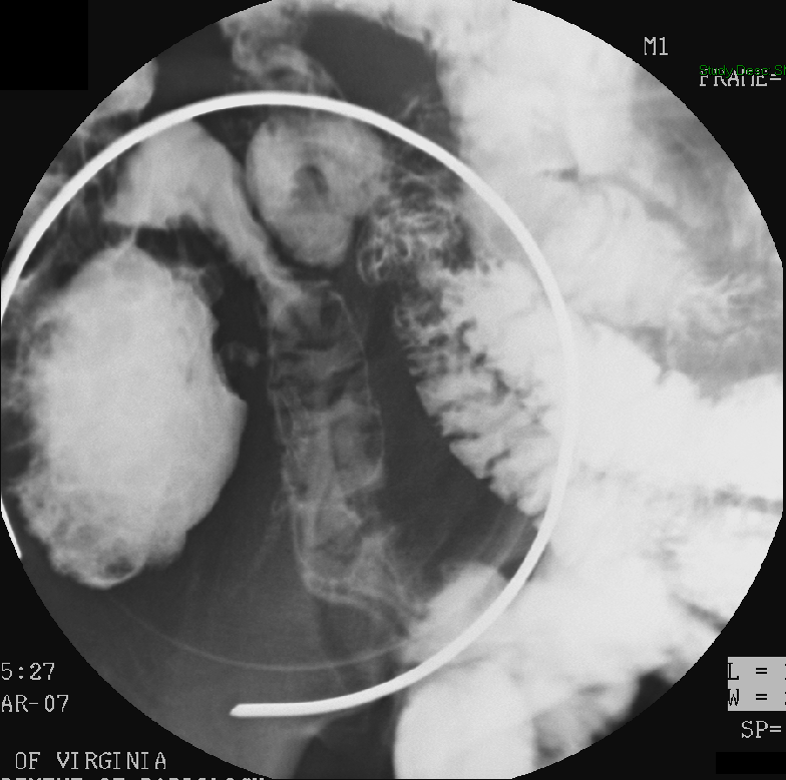

- The technologist will obtain a scout radiograph to include the upper abdomen. Evaluate for the location of the surgical chain sutures

(key image 1).

- There are usually two "sets" of surgical chain sutures.

- The first is located in the epigastric area at the level of the gastrojejunal anastomosis.

- The second is usually located in the left midabdomen. This is the site of the jejunojejunal anastomosis.